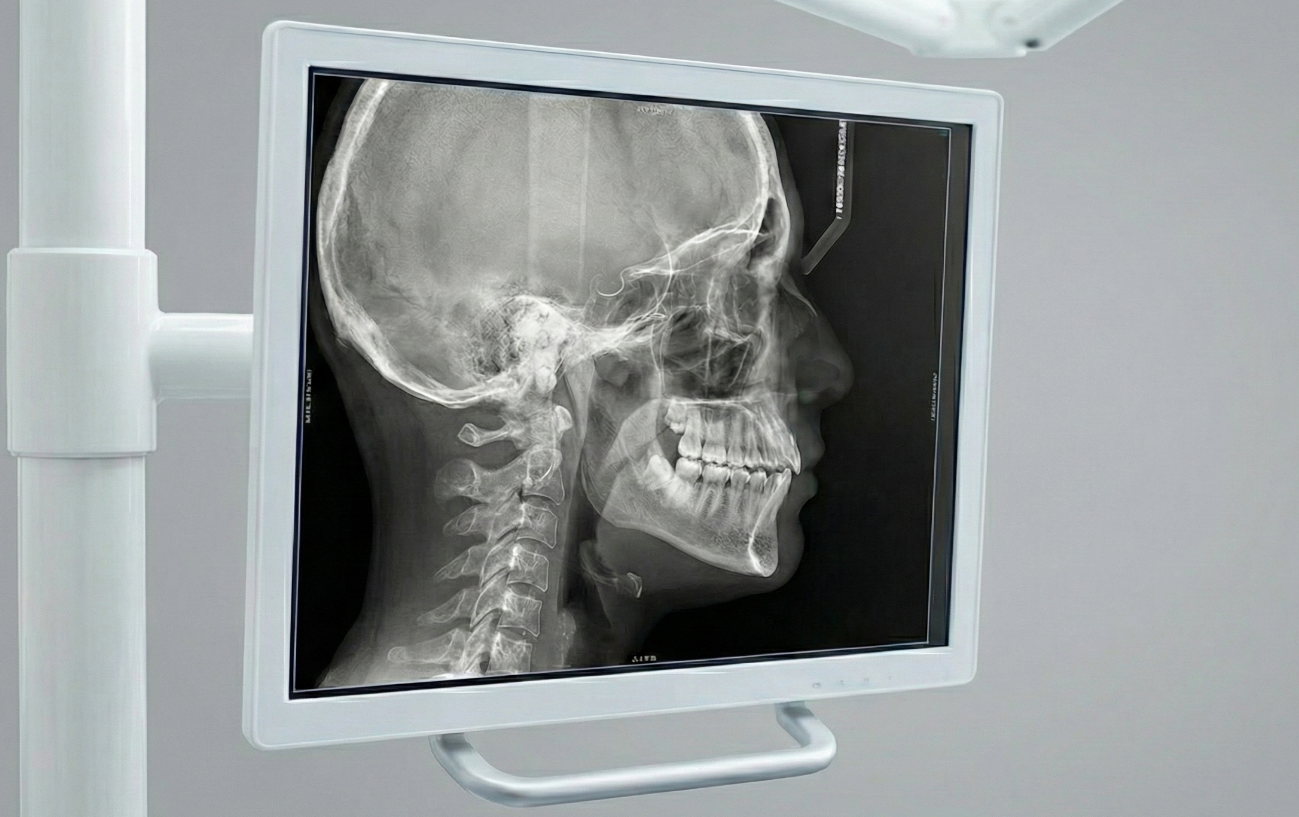

Radiografías Cefalométricas

Proporcionan un perfil lateral del cráneo y los dientes. Se utiliza principalmente en ortodoncia para evaluar el crecimiento facial y son parte de las radiografías utilizadas para planificar tratamientos de ortodoncia.